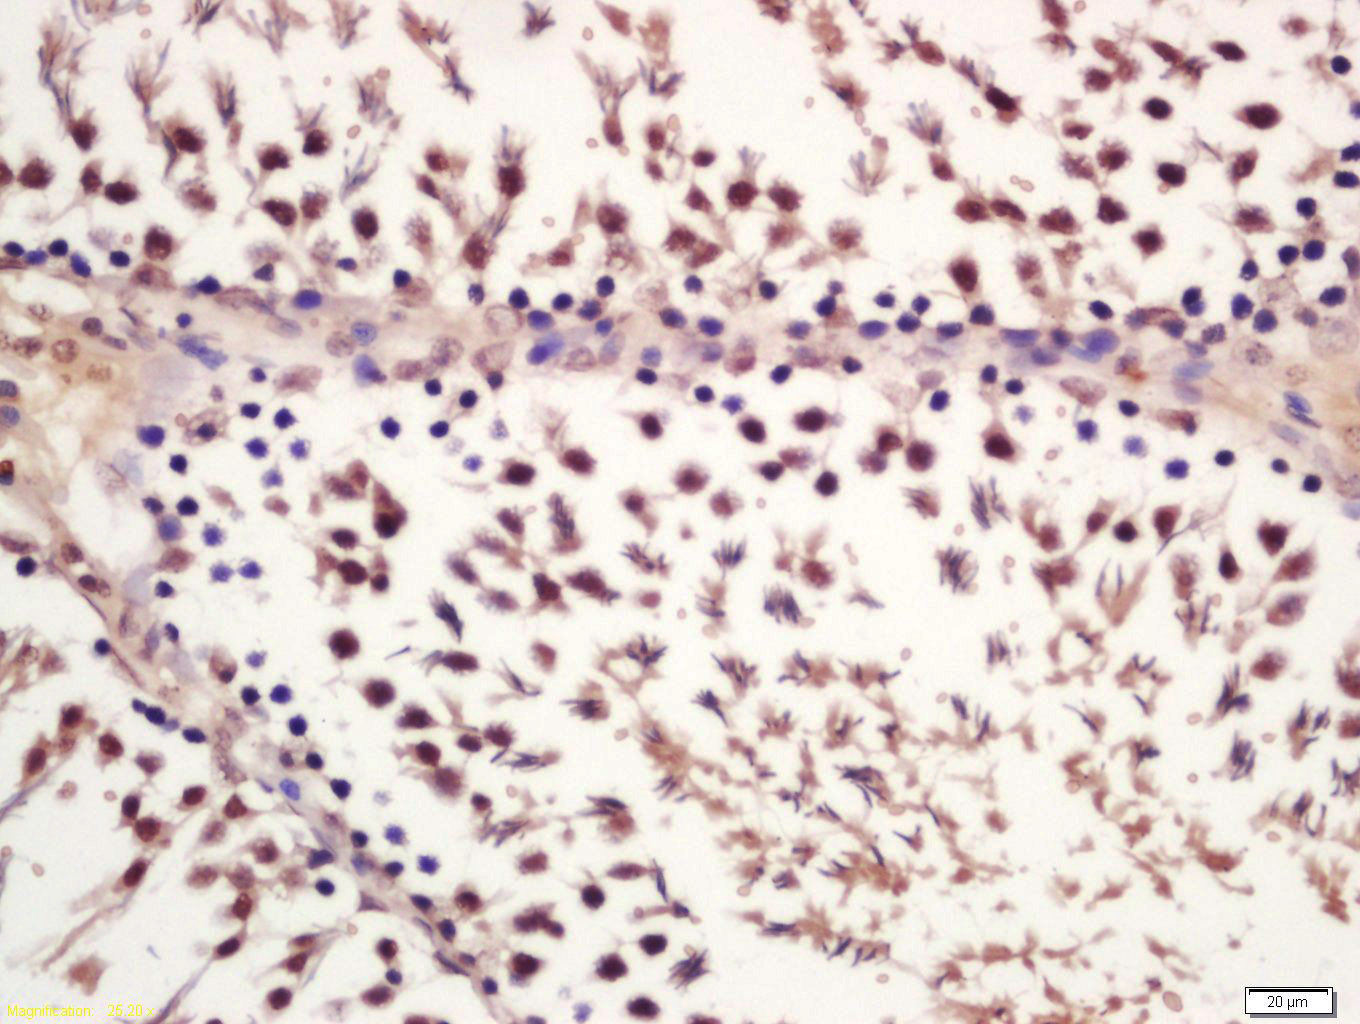

Tissue/cell: rat testis tissue; 4% Paraformaldehyde-fixed and paraffin-embedded; Antigen retrieval: citrate buffer ( 0.01M, pH 6.0 ), Boiling bathing for 15min; Block endogenous peroxidase by 3% Hydrogen peroxide for 30min; Blocking buffer (normal goat serum,C-0005) at 37℃ for 20 min; Incubation: Anti-phospho-GSK-3 Beta(Ser21) Polyclonal Antibody, Unconjugated(bs-5368R) 1:200, overnight at 4°C, followed by conjugation to the secondary antibody(SP-0023) and DAB(C-0010) staining